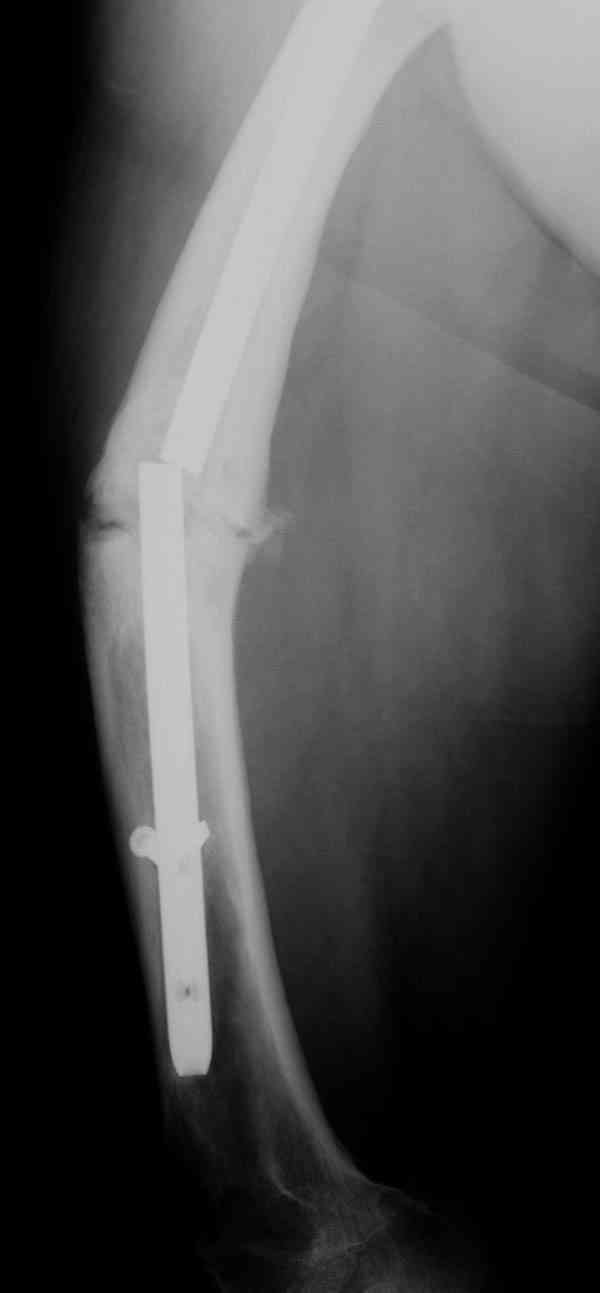

Сросшаяся малоберцовая как распорка привела к образованию ложного

сустава. В таких случаях удаляем сломанный штифт и проводим

стимуляцию ложного сустава рассверливанием. Рассверливание канала

создает стимуляцию на месте ложного сустава, и динамический вариант

блокировки штифта с большим диаметром создаст стабильность. Ранняя

нагрузка после остеотомии малоберцовой приведет к сращению ложного

сустава.